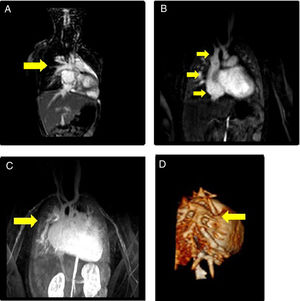

Caso clínicoSe trata de un niño de 3 años sin cardiopatía previa conocida, que comienza con cuadro de insuficiencia cardiaca congestiva secundaria a miocardiopatía restrictiva y DVPAP derecho a vena cava superior sin comunicación interauricular (CIA), que evoluciona hacia fase terminal. Elevación de presiones de llenado derechas e izquierdas, resistencias pulmonares normales, disfunción diastólica restrictiva severa del ventrículo izquierdo y presencia en la resonancia magnética cardiaca de drenaje venoso anómalo de lóbulos pulmonares derechos superior y medio, con dilatación significativa de ambas aurículas y del ventrículo derecho (fig. 1).

Imágenes de resonancia magnética (A-C son cortes sagitales): A) Arteria pulmonar. B) Vena cava superior, aurícula derecha y vena cava inferior. C) Desembocadura de venas pulmonares (VVPP) anómalas a vena cava superior. D) Reconstrucción tridimensional de la llegada de las VVPP anómalas a vena cava superior.